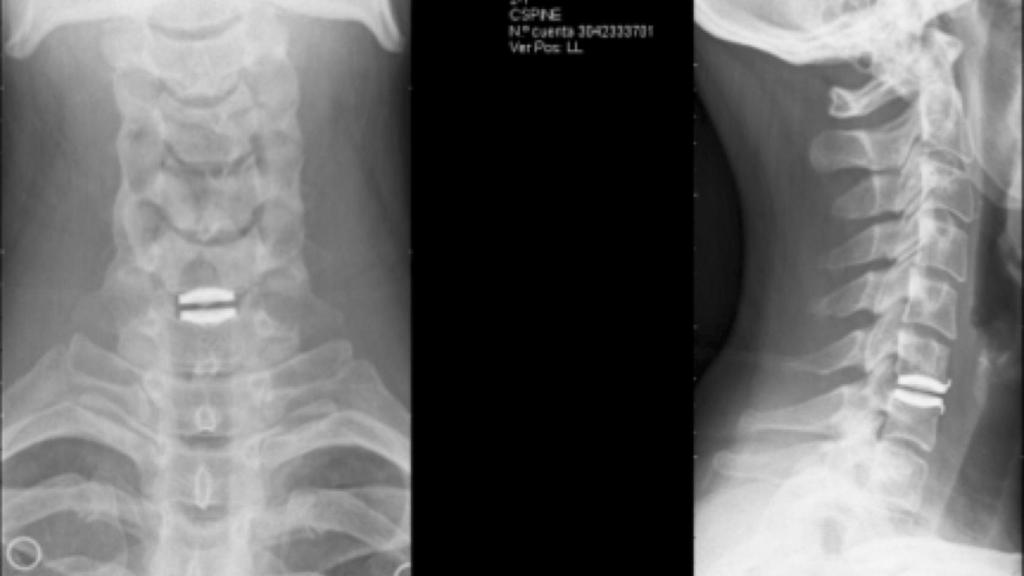

Año XVIII. "Aquí se me salió el disco, en una grave caída, cuando por primera vez iba a representar a mi país en Francia. Una placa de hielo, vueltas de campana. Caí con la cabeza. Yo tenía una hernia de disco y se me salió. Mi padre decía "por lo menos ahora dejarás de esquiar". Y dije: "Ah, no". La libertad que siento ahí es incomparable. Ahí recupero mi gusto por la velocidad" (2008).